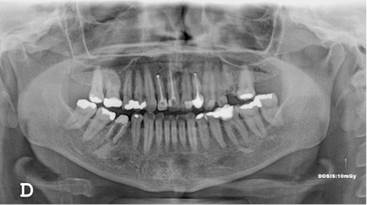

Los resultados mostraron que en el 48 % de la población se encontró algún hallazgo relacionado con la pulpa dental, con frecuencias similares entre hombres y mujeres, siendo el tratamiento endodóntico el más frecuentemente encontrado (Tabla 1, Fig. 1). El rango del número de endodoncias por radiografía fue de 1 a 18. El 86,4 % de las radiografías presentaron de 1-5 endodoncias, 11,4 % de 6-10 y el 2,2 % de 11-18. La presencia de zona radiolúcida periapical seguida por la reabsorción (Fig. 2), fueron los siguientes hallazgos más frecuentes. (Tabla 1)

Los otros hallazgos analizados (Fig. 3) se presentaron en muy baja frecuencia. Para ninguno de los casos, se encontraron diferencias estadísticamente significativas entre hombres y mujeres.

Un total de 1.590 dientes que tenían tratamiento endodóntico, se clasificaron según su estado: el 44,9 % de los dientes presentaron endodoncias en buen estado, mientras que aproximadamente la mitad de ellos se encontraron subobturados (52,7 %) y el 2,5 % sobreobturados. El 95.6 % de los dientes tratados endodónticamente, presentaban algún tipo de restauración.

Cuando se analizó la frecuencia de tratamientos endodónticos por el tipo de diente, se encontró mayor frecuencia en dientes del maxilar superior (69,1 %), siendo los más tratados los primeros molares superiores e inferiores en ambos maxilares y los centrales superiores (Gráficos 1 y 2).